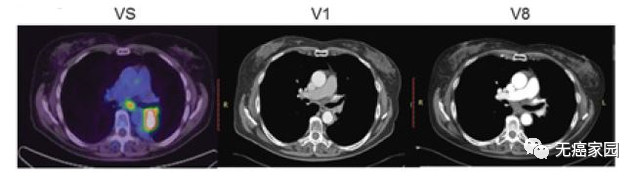

本研究中,采用局部输注 NKG2Dp CAR-NK的方式治疗了3 例转移性结直肠癌患者。前两例患者腹腔输注低剂量 CAR-NK 细胞后,可观察看腹水生成量减慢以及腹水样本中肿瘤细胞的数量急剧减少。第三例肝转移瘤患者采用超声引导下瘤内经皮注射和腹腔内灌注方式输注 CAR-NK细胞后,多普勒超声可见肝部肿瘤快速缩小,正电子发射断层扫描(PET-CT)提示经治疗的肝病灶为完全代谢反应。3 例患者在治疗过程中均无出现3级或以上的不良事件。

CAR-NK 细胞治疗后肝转移病灶 PEC-CT 结果对比图

(患者肝Ⅵ段的最大氟脱氧葡萄糖(FDG)摄取值从 8.2 降至 0.14,经评估为完全代谢缓解)